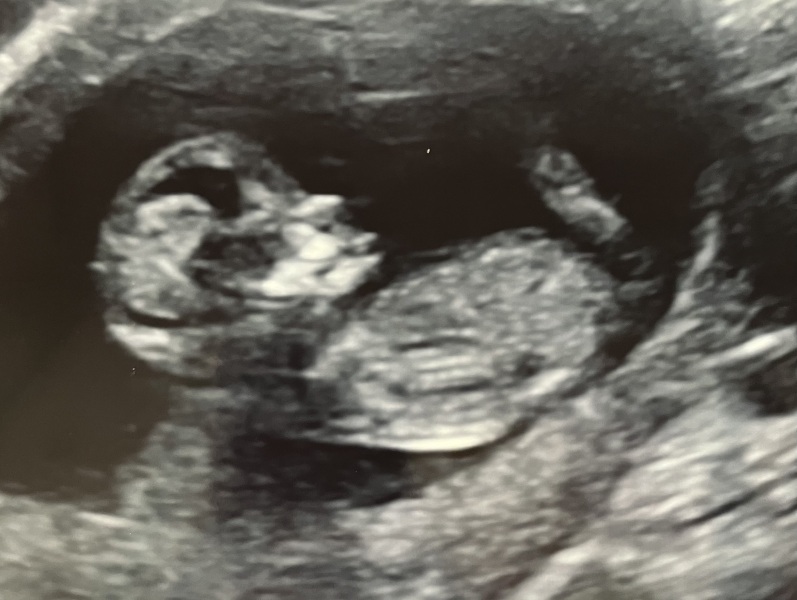

Had my 12 week scan today, measuring ahead of what I thought! They were so wriggling! It was lovely to see!

Congratulations 🫶🏻😍 does definitely look wriggly! X